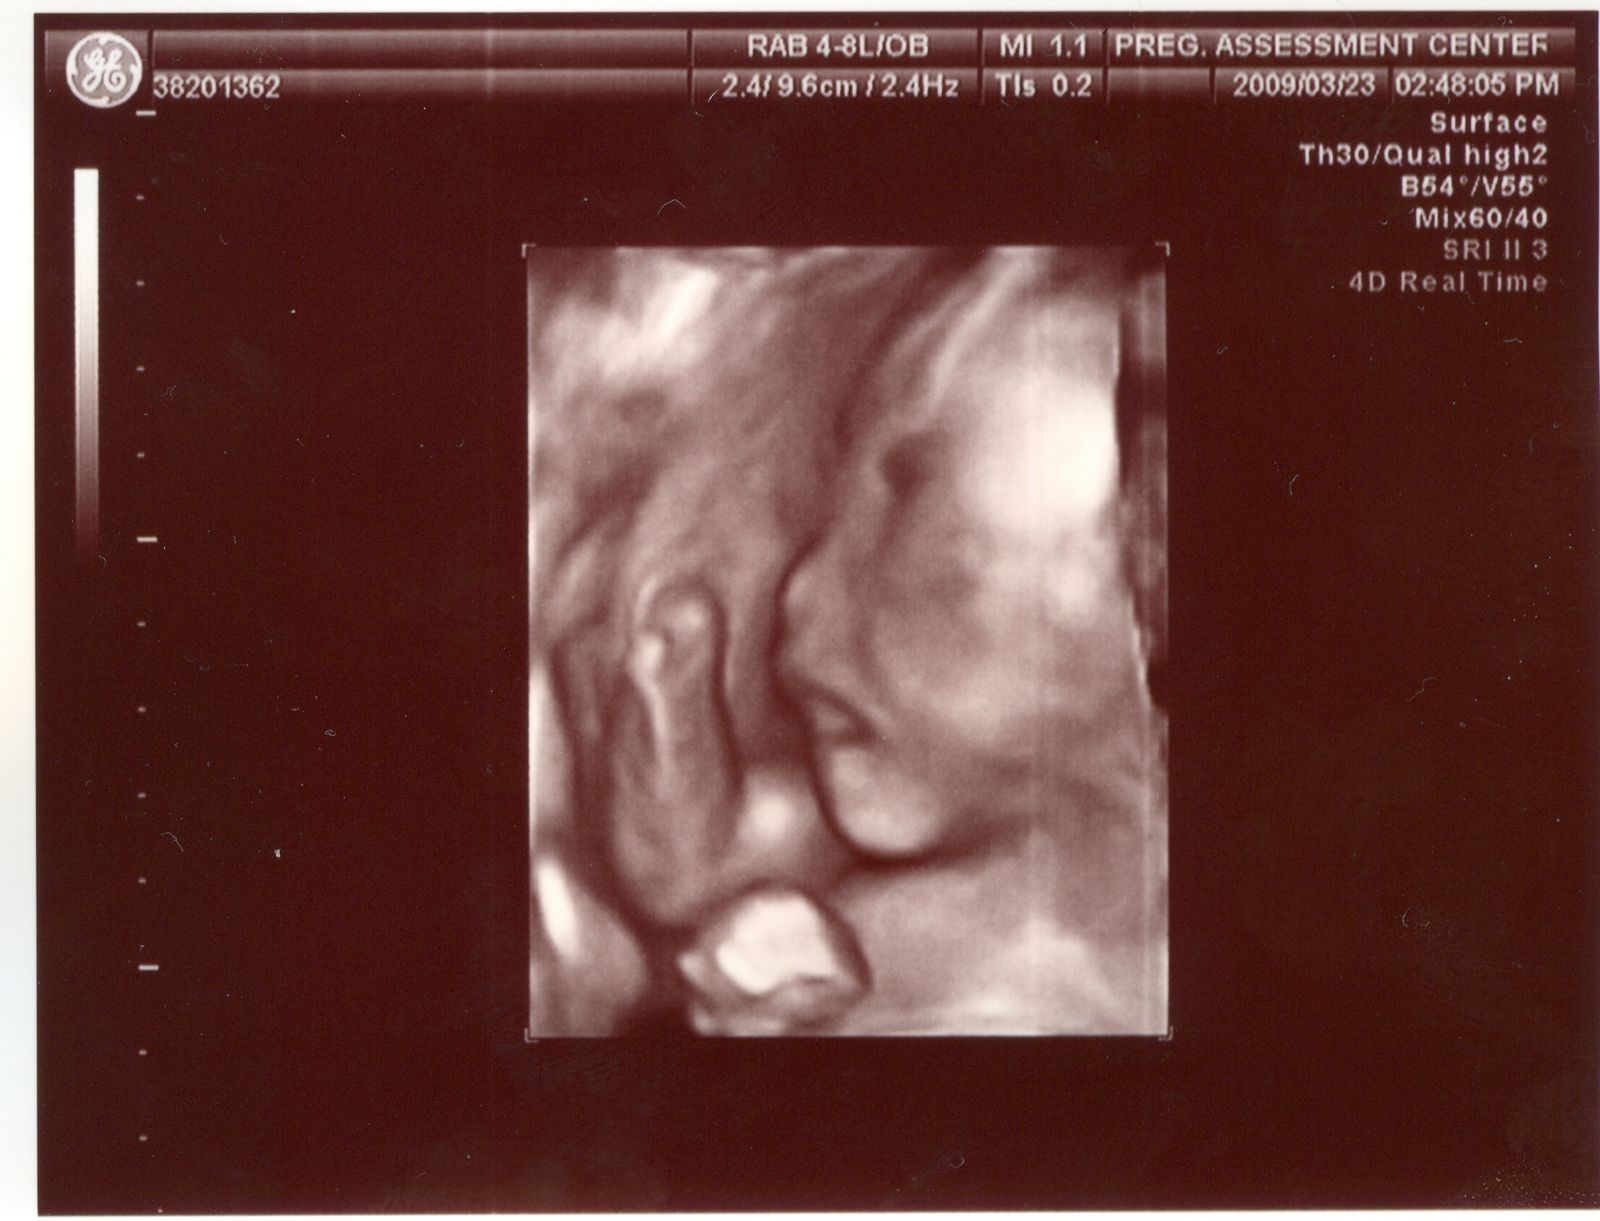

除了看到傅小妹的五官,醫生還看到他淘氣的用腳腳在踢臍帶,這次也有印出他的小腳丫,不過還是上次的比較漂亮喔!

踢臍帶的傅小妹 |